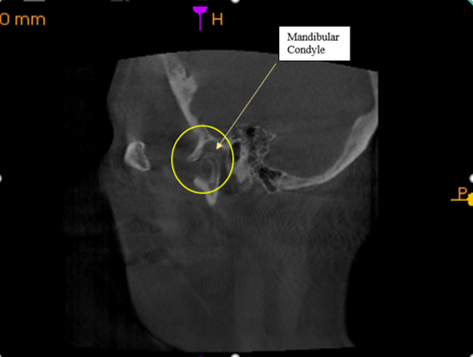

Right side view, normal; where the mandibular condyle should be.